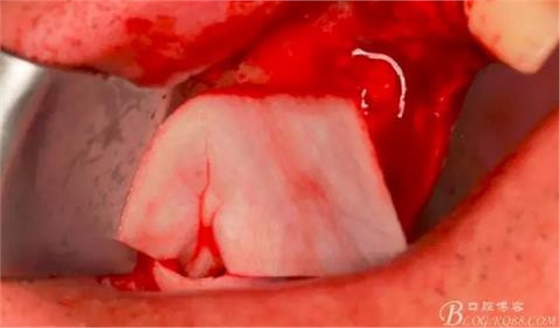

此時(shí)頰側(cè)竇膜與骨壁已經(jīng)分離,無需擔(dān)心開窗損傷竇膜。使用環(huán)切鉆以小洞口為中心開窗,轉(zhuǎn)速500轉(zhuǎn),為了保證安全,可以將種植機(jī)調(diào)成反轉(zhuǎn)模式,一樣有強(qiáng)大的切割效率。